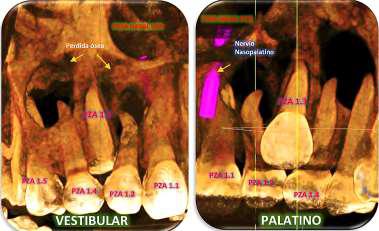

RECONSTRUCCION 3D DE LA ZONA A ESTUDIAR

Las reconstrucciones tridimensionales nos permiten una visualización detallada y precisa de las estructuras vecinas a la pieza retenida, superando las limitaciones 2D de las radiografías convencionales, también ayudara en este caso para la planificación quirúrgica y posterior tratamiento de ortodoncia.

En este caso podemos observar una lesión de diámetro considerable de bordes corticalizados y forma irregular proyectada en el maxilar superior en el cuadrante 1, que se extiende desde distal de la pieza 1.1 hasta distal de la pieza 1.5, desde el tercio apical de las piezas 1.2 – 1.4 y 1.4 por vestibular y desde cervical por palatino. Se evidencia también a la pieza 1.3 retenida desplazada el ápice hacia la cortical palatina y la corona hacia la cortical palatina

CORTES AXIALES

Con la evaluación de la tomografía volumétrica en cortes axiales y transversales se observa la expansión y adelgazamiento de la tabla ósea vestibular y palatina legando a dicha pérdida ósea, también se observa el desplazamiento de la pieza 1 3 la cual se encuentra retenida y desplazada hacia la basal vestibular.

CONCLUSION

CORTES SAGITALES

A nivel de los cortes sagitales y coronal verificamos la extensión de la lesión y evidenciar el desplazamiento de las piezas 1.2 a mesial y 1.4 hacia distal a causa de la retención de la pieza 1.3 y expansión de la lesión